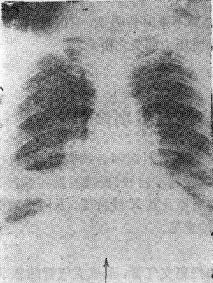

2.支气管腔外压性梗阻 如淋巴结肿大、血管环压等图115-1右下肺不张

右下肺不张

图115-1 右下肺不张